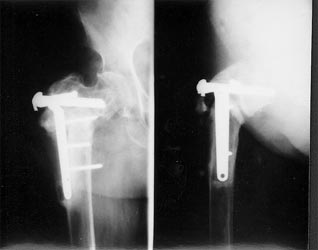

有的病例采用DHS治疗,同时采用骨髓细胞和植骨复合物植入。成功治愈患者。

患者股骨粗隆下骨折、骨不连,左图为手术前,显示假关节形成,右图为手术内固定后,关节功能恢复